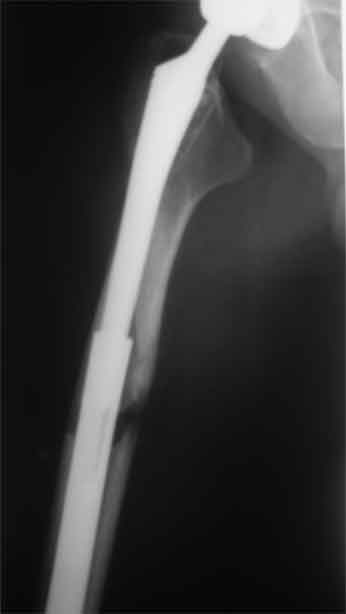

А нельзя ли увидеть и профиль бедра на всем протяжении, т.е. и весь протез, и весь стержень? И фас бы с коленом.

igor 20 Ноябрь 2009, 08:08

новые снимки